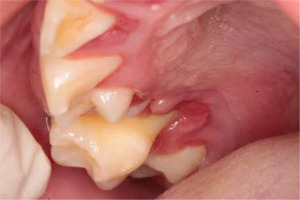

When the patient was 10, the exposure of two-thirds of palatal roots and third-degree loosening of teeth were observed (Fig. 3). A panoramic radiograph picture was taken (Fig. 4), which revealed complete absence of the bone base in all permanent first molars. Teeth 16 and 26 were qualified for extraction, which was performed in an outpatient setting under local anesthesia and antibiotic treatment (clindamycin, 10 mg/kg/dose). The obtained material from granulomatous lesions was submitted for histopathological examination, the results of which indicated non-specific inflammatory granulation tissue.